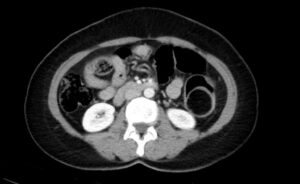

Adult Intussusception. CT Axial Unannotated. JETem 2024